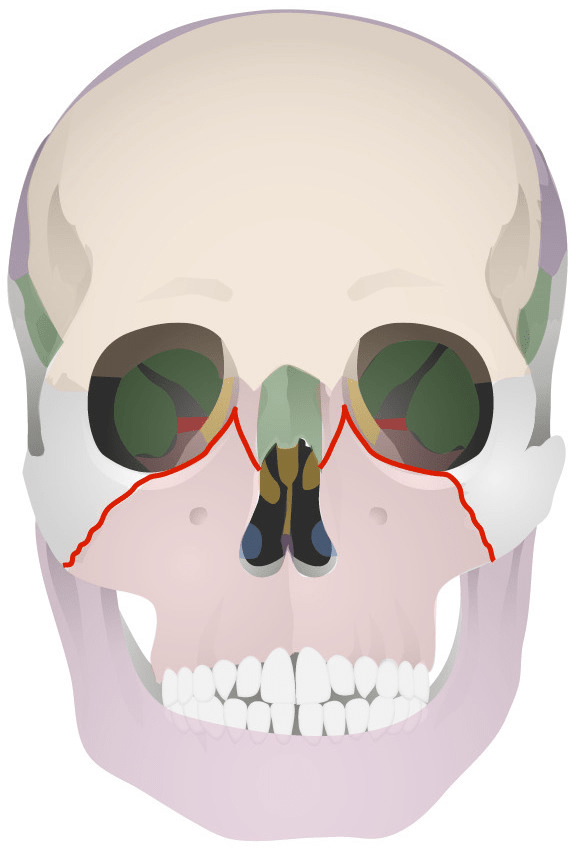

Name this Classification of facial injury?

Le Fort II (Maxilla and nose move)